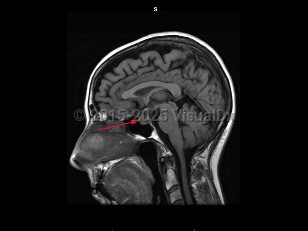

CraniopharyngiomaCraniopharyngioma